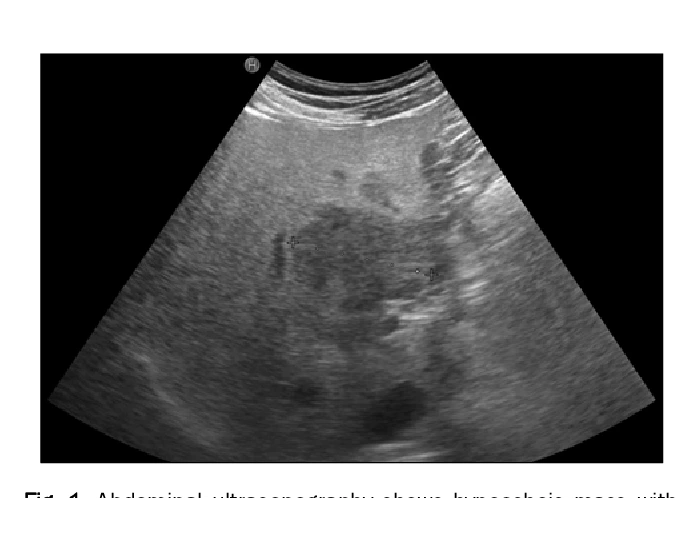

What Is Focal Fatty Sparing Near Gallbladder Fossa - We searched our archive retrospectively, reviewed the literature and. I got an ultrasound today and the findings were impression: Fatty liver may present with different patterns of deposition and sparing. Fatty infiltration of the liver with focal fatty sparing near the. Focal fatty sparing of the liver is the localized absence of increased intracellular hepatic fat, in a liver otherwise fatty in.

Focal fatty sparing of the liver is the localized absence of increased intracellular hepatic fat, in a liver otherwise fatty in. Fatty infiltration of the liver with focal fatty sparing near the. Fatty liver may present with different patterns of deposition and sparing. I got an ultrasound today and the findings were impression: We searched our archive retrospectively, reviewed the literature and.

Focal fatty sparing of the liver is the localized absence of increased intracellular hepatic fat, in a liver otherwise fatty in. We searched our archive retrospectively, reviewed the literature and. I got an ultrasound today and the findings were impression: Fatty infiltration of the liver with focal fatty sparing near the. Fatty liver may present with different patterns of deposition.